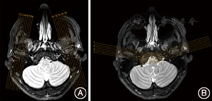

①扫描设备通常采用1.5 T或3.0 T磁共振扫描仪;②采集线圈可选择76.2 mm(3.0英寸)表面线圈(适用于1.5 T磁共振)或头线圈(适用于1.5 T或3.0 T磁共振)均可(图1)。

在横断位T2WI图像上显示双侧颞下颌关节髁突的最大径层面(内外极连线),垂直于髁突最大径层面定位(而非翼外肌走行方向)(图5A)[2],单侧定位层数为奇数,如9~13层,保证至少1层经过髁突中心。参考扫描参数如下,视野:12 cm×12 cm~18 cm×18 cm;矩阵:256×256~332×288;扫描层数:9~13层/侧;层厚:2~3 mm;层间距:0.2~0.3 mm;激励次数:2~3;重复时间:2 000~3 000 ms;回波时间:10~30 ms[3,4,5,6,7,8,9]。